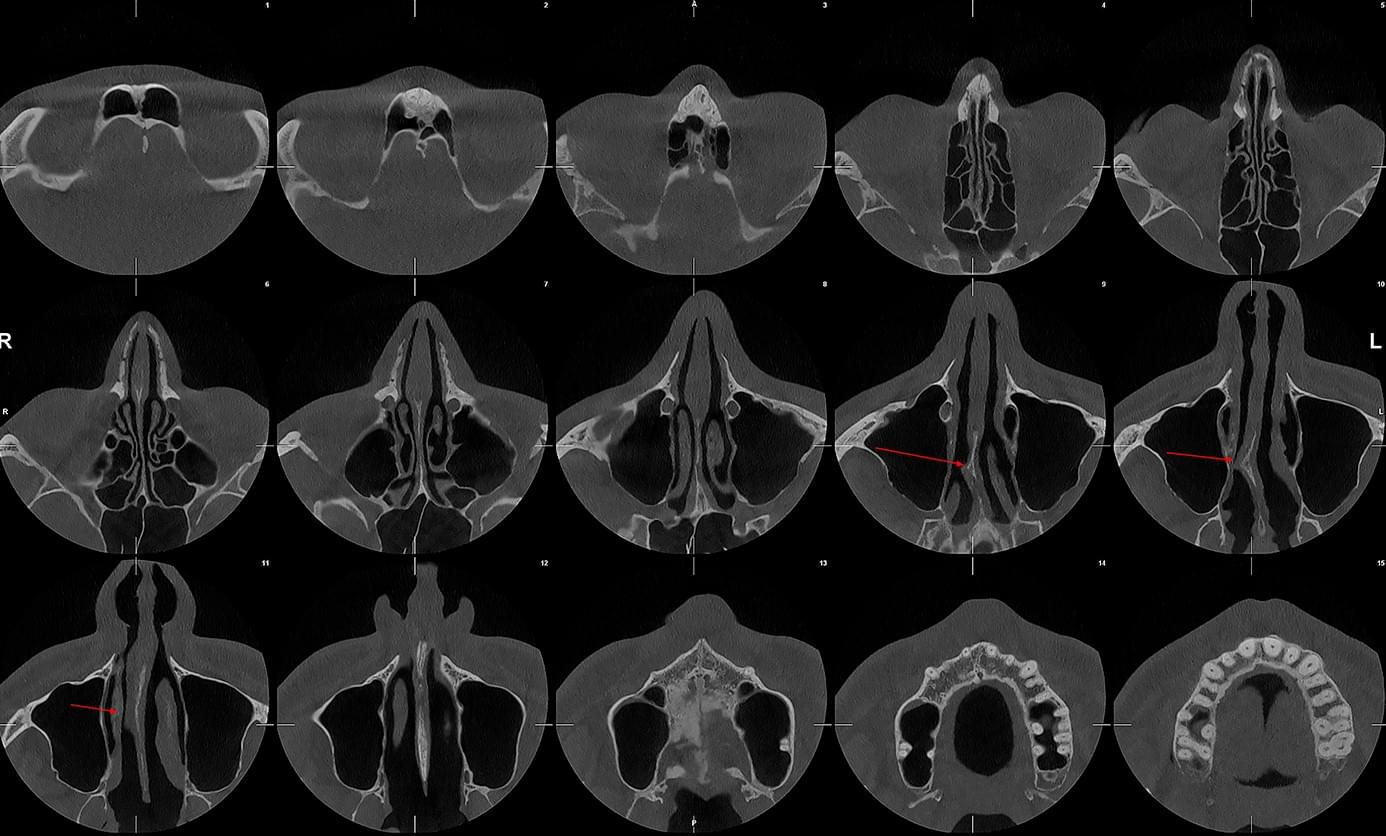

Діагностика гайморових пазух за допомогою КТ

У сучасній медицині КТ придаткових пазух носа (або КТ синусів) — це «золотий стандарт»

діагностики для ЛОР-лікарів та щелепно-лицевих хірургів. Звичайний рентген часто не

показує повну картину, а МРТ не завжди доступний і дорожчий. Комп’ютерна томографія дає

детальну 3D-модель усіх пазух (гайморових, лобних, клиновидних та решітчастого

лабіринту) за 10 секунд і з мінімальною дозою опромінення.

КПКТ (конусно-променева комп’ютерна томографія) — це 3D-знімок високої роздільної здатності. На відміну від звичайного рентгену, КТ показує: